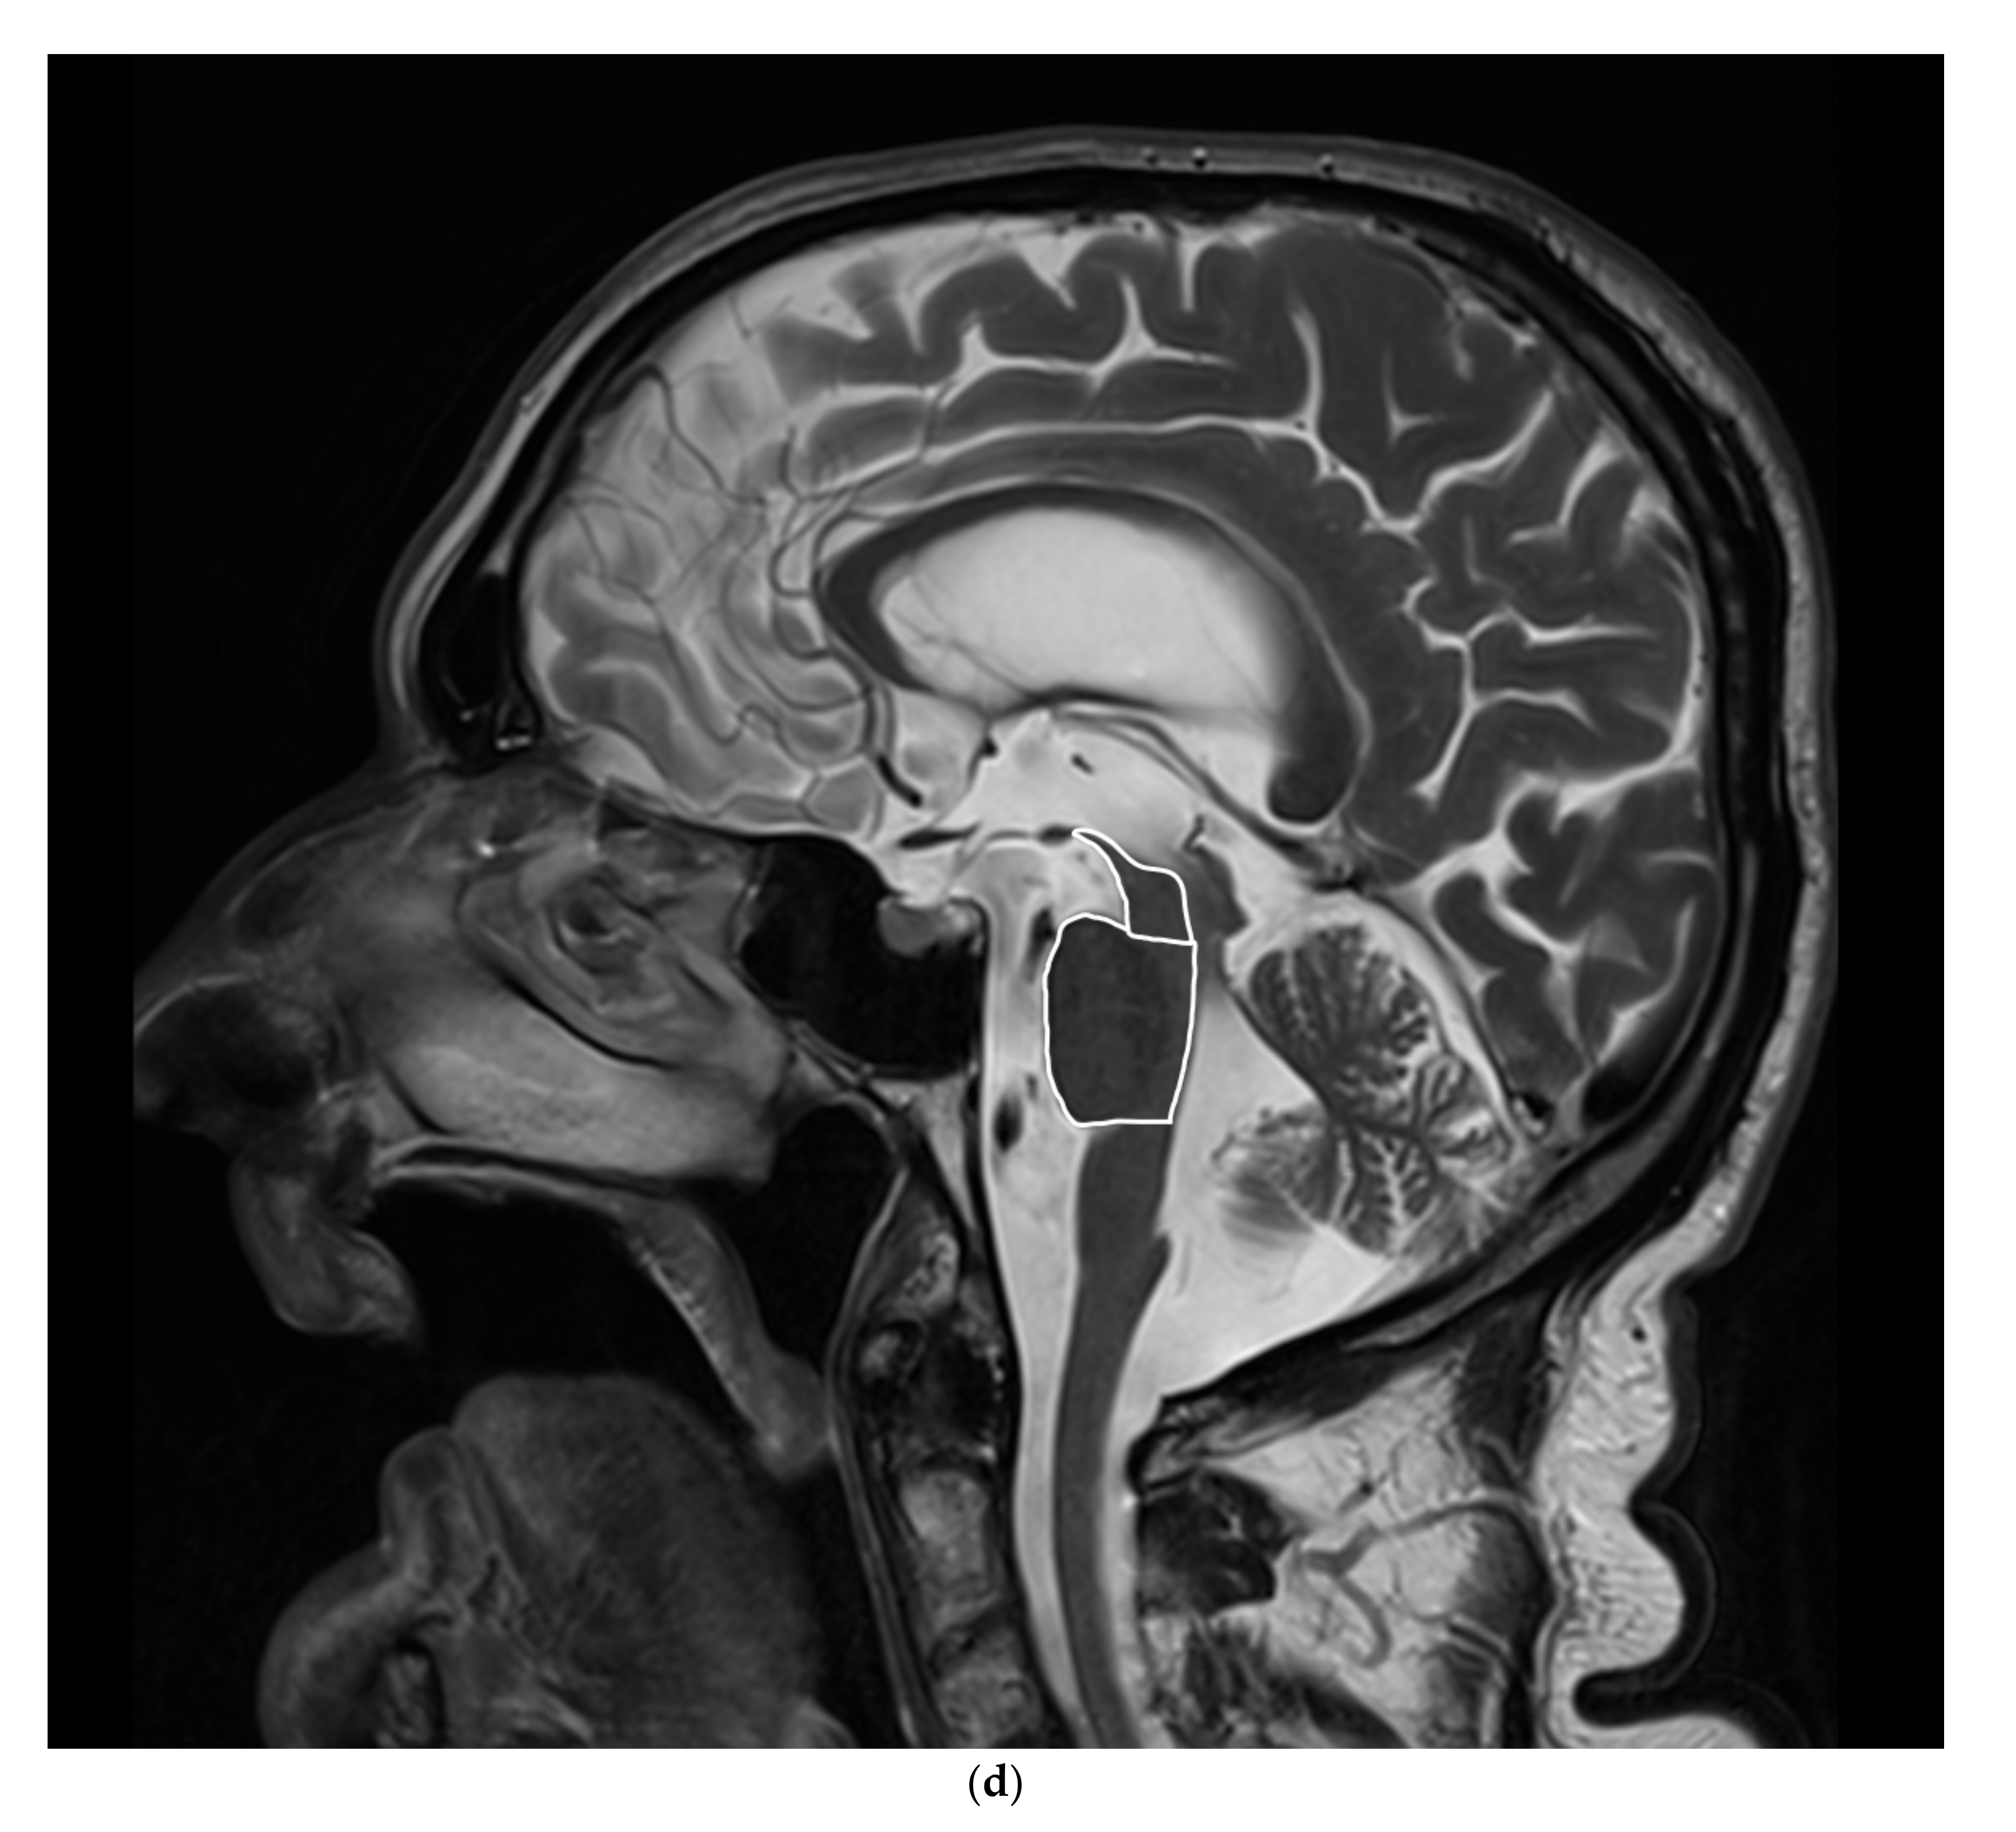

3.1. MRI

5.1.2. MRI